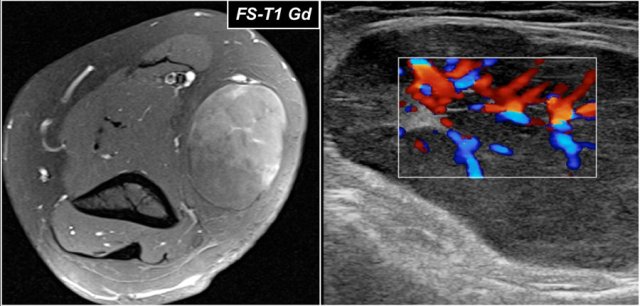

Here are the ultrasound images of a 73 year old male who experienced a sudden pain and a tearing sensation when lifting a box.

There was pain with pronation and supination and tenderness anteriorly proximal to the elbow joint.

No ecchymosis or palpable mass.

On the sagittal image the tendon is thickened, but distally the tendon is lost.

MRI examination was performed.

Now look at the MR-images and try to figure out if the tendon is retracted and whether there is a partial or complete tear...

Well on the sagittal image it looks as if the tendon is completely thorn, but continue with the next images.

Tear of distal biceps tendon

There is a complete tear, because if we follow the tendon all the way to the radial tuberosity, we can see that the tendon does not attach there (green arrow).

There is only fluid.

The reason why the tendon is not retracted is because the broad bicipital aponeurosis - also known as lacertus fibrosus - is still intact (red arrow).

The distal biceps tendon not only inserts to the radial tuberosity, but also via the lacertus fibrosus into the fascia of the flexor pronator mass on the medial side of the forearm.

The distal tendon of the biceps is encircled on the upper left image.

When the aponeurosis is also thorn, then the tendon retracts and you get an obvious swelling in the arm caused by the contracted biceps muscle.